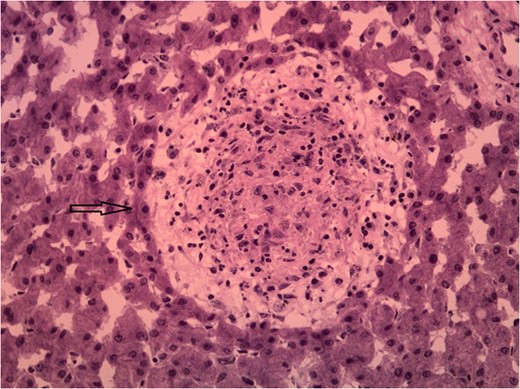

Granulomas are focal accumulations of epithelioid cells, typically with a rim of lymphocytes and fibroblasts, representing a delayed-type hypersensitivity reaction in response to antigenic stimulation. This stimulation is usually triggered by exposure to antigen that cannot be degraded or in cases of immune dysfunction [1].

Unfortunately, liver granulomas rarely present with distinct histological features enabling pathologic diagnosis [2]. Studies have shown that 6–15% of granuloma findings are idiopathic [1, 2]. Few histological features associated with certain diseases include caseous necrosis in acid fast bacilli containing granulomas, or ova in Schistosoma mansoni [1].

Humans are infected when larvae in contaminated freshwater penetrate the skin. Once infection occurs, the adult worms reside in veins releasing eggs that are either shed into the environment through feces or urine, or are retained in host tissues where they induce inflammation and then die. When Schistosoma eggs are trapped in tissues, they activate an immunologic reaction leading to the development of granuloma and fibrosis [6].

Hepatic schistosomiasis leading to severe fibrosis is a well-recognized cause of chronic liver disease and portal hypertension. It results from the host’s granulomatous cell-mediated immune response to the ova antigen and progressing to irreversible fibrosis [7]. Multiple factors influence the development and pathology of Schistosomiasis including the type of immune response developed by the host, host genetic background, intensity and number of infections [8]. Most schistosomiasis is caused by Schistosoma Hematobium, S. mansoni and S. japonicum; however, S. mansoni and S. japonicum tend to cause hepatobiliary disease, while S. hematobium mainly affects the urinary tract [6]. Due to the life cycle of Schistosoma, the acute phase of infection is usually asymptomatic, the only chronic sequelae identified via tissue biopsy is necrotic eggs with granuloma formation. Thus, disease transmission is unlikely.